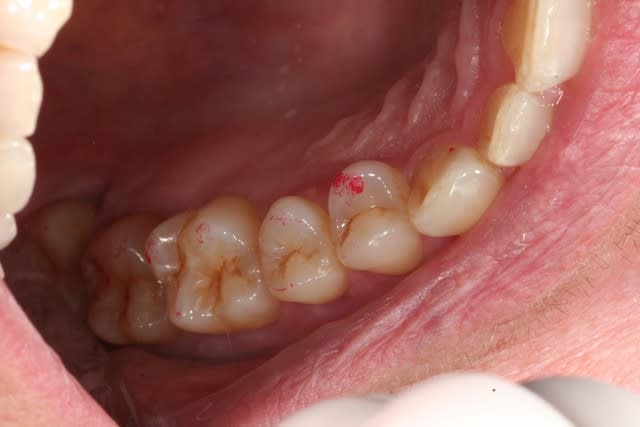

voilà les images en OIM.

et la suite....

Oim haut droite qjqccc - Eugenol

Oim haut gauche rtfqsa - Eugenol

Oim molaires d eslwjz - Eugenol

C'est ainsi que je l'avais imaginé, reprends sur les prémolaires au soflex rouge gros grains ou au carborandum vert bouteille... Quand je regarde la panoramique dans son ensemble, je vois la perte des dents à droite, je vois la perte osseuse au niveau des molaires maxillaires droites, je vois les diastèmes par ci par là, je me dis qu'elle presse les dents la vieille dame, je me dis aussi qu'il doit y avoir nécessairement surcharge quelque part, les photos que tu me montres tendent à incriminer les premières prémolaires maixillaires, commence par là tu ne peux pas te tromper, après correction fais la déglutir deux trois fois, fais lui avaler de l'eau, dis lui de faire une vasalva histoire de voir si les delta de pression se lèvent ensuite lors de la nouvelle pim suivie d'une déglutition redevenue normalement fonctionnelle au niveau tubaire, ensuite tu devrais pouvoir disposer des filtres pour aller plus finement dans l'examen de la fonctionnalité des cochlées...